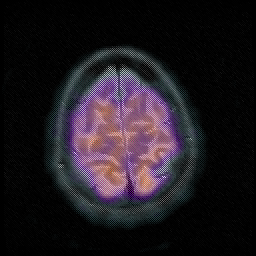

Huntington's Chorea, MR -- Slice #18

[Home][Help][Clinical] Slice 18